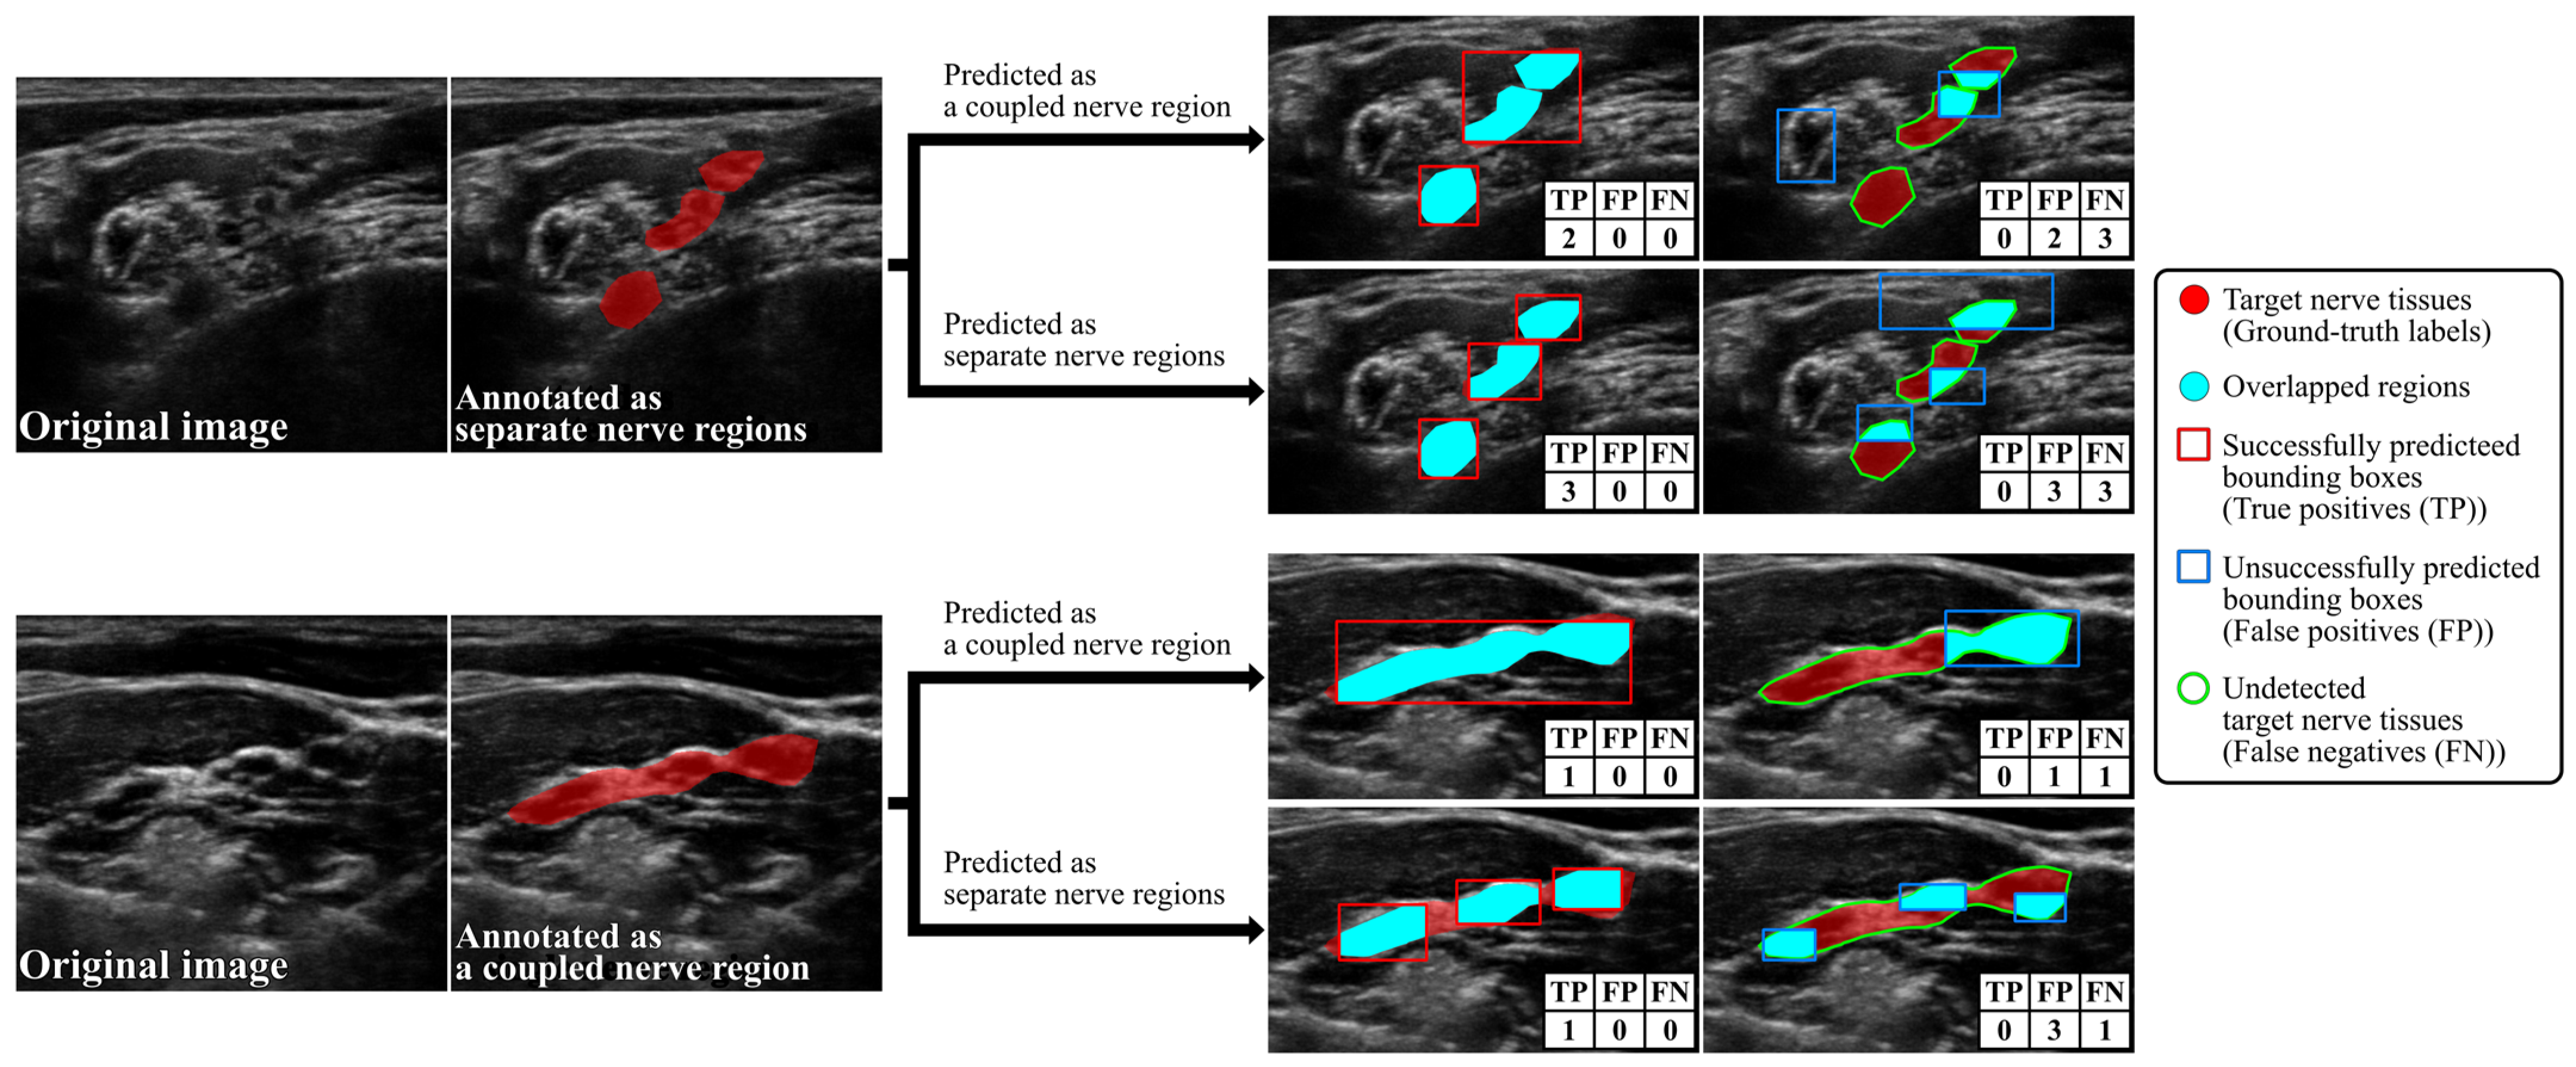

3.2. Evaluation Metrics